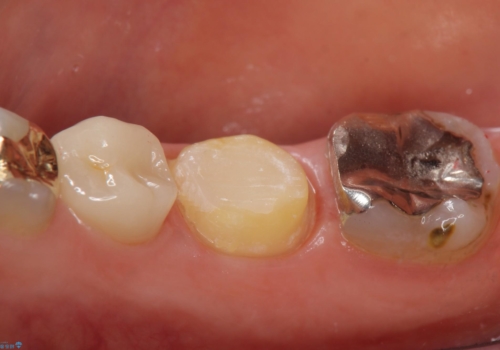

- 右下の奥歯でものを咬むと違和感があるので診て欲しいといらっしゃった方の症例です。

右下6は神経が死んでいたため根管治療を行い、オールセラミッククラウンによる補綴を行いました。

右下7は冷たいものがしみていたため、銀歯を除去後、オールセラミッククラウンによる補綴を行いました。